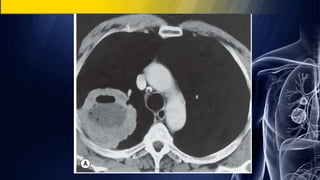

PA chest radiographs demonstrate a well defined spherical pulmonary mass of lobular contours

in the left lung

Contrast-enhanced chest CT (mediastinal window) at the level of left atrium demonstrates a

heterogeneously enhancing mass with irregular central low attenuation, representing necrosis.

The mass abuts central bronchi medial and the adjacent pleura laterally

65-year-old man with cough and chest pain

Lung Cancer